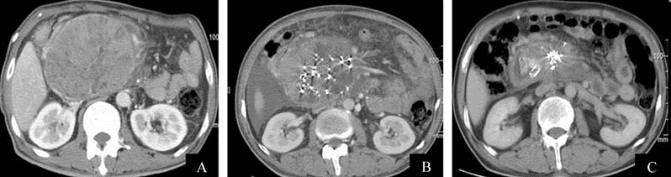

图21-30 125I粒子置入治疗胰腺癌

A.治疗前CT示胰头巨大肿块;B.125I粒子置入后;C.复查示肿瘤明显缩小

放射性粒子组织间近距离治疗是将具有杀伤肿瘤细胞作用的放射性125I粒子直接置于肿瘤组织内进行内照射,其以较好的临床疗效、独特的剂量分布优势和放射生物学特点,已成为肿瘤综合治疗中的一项热门技术(图21-30)。其主要应用于无法手术或不愿、不宜手术的原发肿瘤;肿瘤手术不彻底,术中置入;不宜手术的转移性肿瘤;转移或原发肿瘤引起的疼痛;外放疗效果不佳或失败;外放疗或化疗剂量不足,也可作为局部剂量补充。